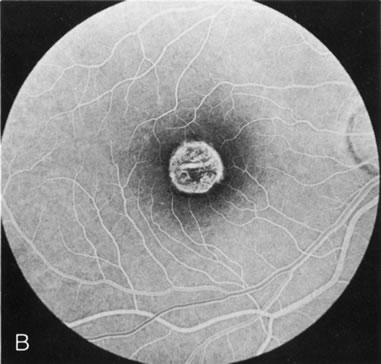

BEST'S VITELLIFORM MACULAR DYSTROPHY

The intact solid yellow egg yolk lesion in Best's vitelliform macular dystrophy (BVMD) typically shows hypofluorescence on FA due to blockage of the underlying choroidal fluorescence with the overlying retinal vasculature visible (Fig. 10A and, B). This finding places the lesion in front of the choroid, possibly within the RPE, but probably not within the neurosensory retina. There is no histopathology of the intact lesion to confirm this.

Fig. 10. Best's vitelliform macular dystrophy. The most characteristic angiographic finding in the solid yellow egg-yolk stage is blocked hypofluorescence (A, B). A morphologically mimicking lesion (pseudovitelliform degeneration) may be the result of leakage from the underlying choroid (C–E).

Histopathology in later stages of BVMD has shown an increase in lipofuscin in the RPE throughout the retina.23 If lipofuscin were within the intact egg-yolk lesion, this would block fluorescence. However, it is surprising that the “silent,” “dark” choroid seen in another disease with diffuse RPE lipofuscin accumulation (Stargardt's disease) does not occur in BVMD.

There are several acquired macular degenerations of different etiologies that have a macular lesion similar to the vitelliform stage of BVMD. FA may be helpful in identifying these cases of pseudovitelliform degeneration by showing leakage from the retinal capillaries or through the RPE and late staining of the lesions (Fig. 10CE). However, the electro-oculogram remains the most discriminating test because it is always abnormal in BVMD and usually normal in pseudovitelliform macular degeneration.